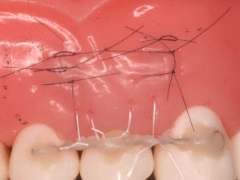

歯周再生治療~カンガルーテクニック~

切断された歯肉を再生することを目的とした治療です。

歯間乳頭の剥離は行いません。

◆治療内容

切断された歯肉を再生することを目的とした治療です。 歯間乳頭の剥離は行いません。

◆リスク

・感染リスクが高まる

・瘢痕による審美性の悪化

◆治療費

保険適用外 20,000円 (税別)